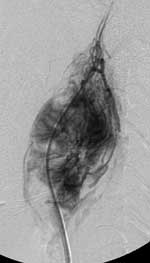

Хирургическое лечение с предоперационной эмболизацией проведено 12 больным. Трем больным с неоперабельными опухолями эмболизация проведена как самостоятельное лечение. Методика проведения эмболизации заключалась в следующем. Больному, у которого имелся предварительный диагноз параганглиомы головы и шеи, либо внеорганной опухоли головы и шеи проводилась цифровая ангиография сонных артерий с двух сторон. Исследование выполнялось на базе ангиографического кабинета НИИ онкологии и медицинской радиологии имени Н. Н. Александрова, оборудованного аппаратом Advantx LCA General Electric Medical Systems. Ангиография выполнялась трансфеморальным доступом по Сельдингеру с катетеризацией общей сонной артерии. Использовались полиэтиленовые катетеры калибром 5–6F, с концевым изгибом Sidewinder, Headhunter, Newton производства фирм Bard-Angiomed и William Cook Europe. Контрастным веществом являлся Omnipaque фирмы Nicomed-Amersham в концетрациях 300 и 350 мг йода на мл. Выполнялась передне-задняя и боковая проекции. Как правило, параганглиома визуализировалась в обеих проекциях (Рис. 1).

[Увеличить]

Рис. 1. В области бифуркации левой общей сонной артерии определяется гиперваскулярная опухоль с девиацией сонных артерий - каротидная параганглиома.